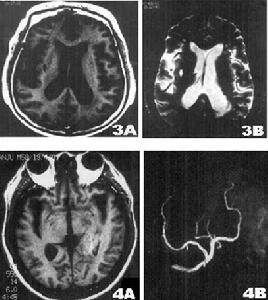

影像學表現:CT表現為斑片狀及斑點狀低密度影,MRI表現為點狀及片狀長T1WI長T2WI信號,由腦深部灰質團塊萎縮,胼胝體繼發變薄,致使腦室擴大,又由於瀰漫性髓鞘脫失而有不同程度的腦萎縮,顯示腦溝增寬,腦池擴大(如圖1~4)。有高血壓及動脈硬化的病理基礎也可發生腦出血是腔隙性梗塞的直接原因。

賓斯旺格病診斷及鑑別診斷:CT,MRI的問世,為本病的生前診斷提供了影像學依據,CT表現為雙側腦室旁白質區與半卵圓中心顯示散在性或融合性低密度區,對稱或大致對稱,基底節,內囊與丘腦區可見多發性腔隙性梗塞,重者伴腦室擴大,其室管膜面多參差不齊,呈碎布狀。MRI表現:在腦室周圍白質與半卵圓中心顯示散在或融合性病變區,T1WI呈黑色,T2WI呈白色。重度與中度顯示腦室擴大,腔隙性梗塞顯影清晰,病灶數目比CT發現的多。SAE應與多發硬化,嚴重腦積水所致的室管膜水腫,CO中毒腦水腫期,腦囊蟲病腦炎型,ALZHEIMER氏病,PICK病,及其他特異性腦白質病,這些腦白質病變根據CT,MRI的表現特點,結合臨床表現60歲以上潛隱起病,逐漸加重,若具備卒中發作,高血壓,慢性進行性痴呆三大臨床特徵,綜合分析,即可做出診斷,也可隨訪複查。

SAE經CT,MRI檢查可明確診斷,CT檢查在發病24h內往往陰性,顯病灶數目少,腦幹,後顱窩病變及視神經通路(視放射)的損害未能顯示而遺漏,但CT價格低,易普及,對腦組織缺氧24h後,CT值即降低,並對缺氧引起的顱內出血及出血量有客觀指標。而MRI在診斷SAE方面比CT更優越,表現在:①MRI在腦細胞毒性水腫6h即可發現病變。②MRI發現病灶數目多。③MRI能夠清楚顯示腦幹,後顱窩病變及視神經通路,顳角部位病變。④MRI可行矢狀,冠狀掃描,多方位觀察。⑤MRI可顯示VIRCHOWROBIN間隙。